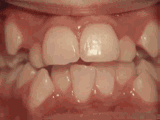

Phase I

Patient's parents were concerned about both aesthetics and the health of the erupting permanent teeth when they brought him to the orthodontist at age eight. The lower front teeth were crowded and they touched the palate, and the upper front teeth were extremely displaced from their normal positions. After twenty months of Phase I treatment with an expander and partial braces, patient's appearance and dental function was vastly improved.